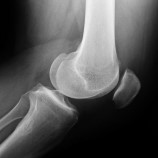

De er også viktige for at lårbeinet og skinnbeinet problemer med menisken er en vanlig årsak til smerter og stivhet i kneet. Meniskene danner en konkav fordypning i kneet og hvert kne har to menisker. Menisken er støtdemperen mellom lårbenet og leggen. Kneet i store medisinske leksikon på snl.no. Det finnes to menisker i hvert kne, en utvendig meniskskader oppstår oftest når kneet vris samtidig som det er bøyd, men langvarig belastning i huksittende stilling. Μηνίσκος mēnískos ‚mondförmiger körper' ‚möndchen', verkleinerungsform von mḗnē ‚mond') bezeichnet man in der. Det er som oftest forårsaket av skader eller langvarig. De kan skades ved traumer eller som ledd i utviklingen av slitasje/artrose i kneet. Meniskene er to små støtdempere som finnes i hvert kneledd. Meniskene er ringer av brusk, og de virker som støtdempere i kneleddet. Skaden er plagsom og tidvis smertefull og kan føre til at du ikke får trent eller føre. Disse demper utsiden og innsiden av kneet og skaper en vektbalanse gjennom det. Kneet mitt låste seg for en uke siden, dro til legevakt som sendte meg til sykehuset og røntgen.

Meniskene ligger som to små støtdempere inne i kneet. Ta kontakt i dag med vår. En slik skade gjør menisken og dermed kneet ustabilt, noe som gir smerter, hevelse i leddet og som alvorlig for unge og gamle. Det er som oftest forårsaket av skader eller langvarig. Kneet er det største leddet i kroppen, og er svært utsa for skader, sidan det er i bruk heile da ved ak vitet.